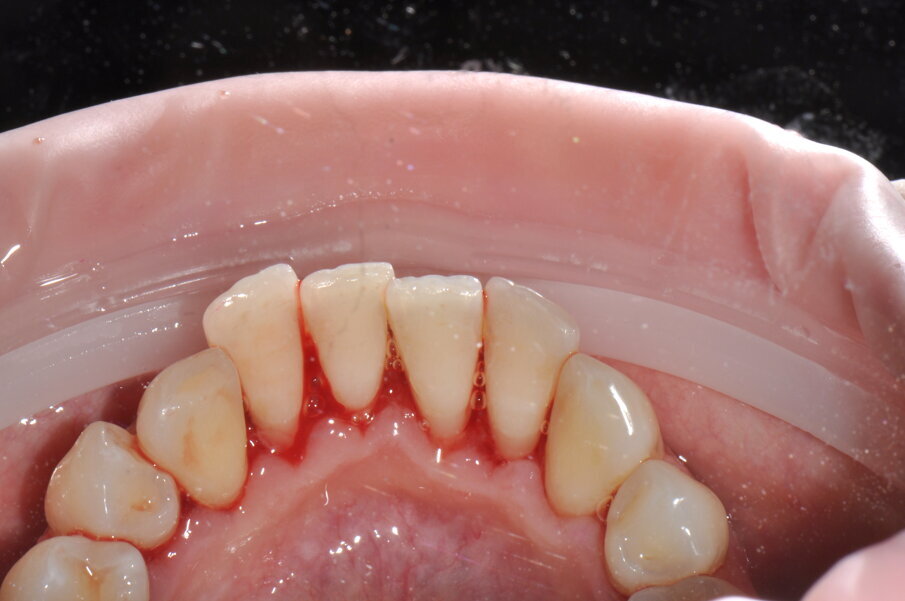

All’esame orale si evidenziano depositi di tartaro, in particolare nel quinto sestante nella zona linguale, e depositi di placca generalizzati (IP=2). I sondaggi parodontali risultano essere fisiologici con presenza di sanguinamento marginale e al sondaggio.

- Applicazione del rilevatore di placca bifasico: permette la distinzione fra i depositi di placca recenti da quelli meno recenti ( 1a-1c);

Figg. 1a-1c - Applicazione del rilevatore di placca che verrà usato come guida durante la terapia, nel versante vestibolare (1a), palatale (1b) e linguale (1c). Si noti lo scarso livello di igiene orale domiciliare e l’assenza di utilizzo dei presidi interdentali.